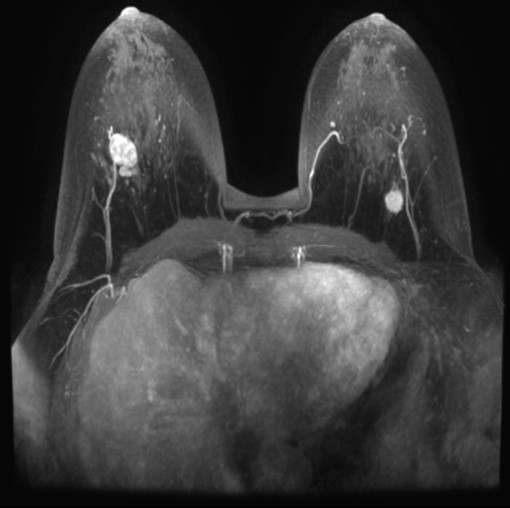

• 右腫瘤

造影で内部均一、漸増型*

Dark internal septationがある

背側に分葉状の部分がある

右 BI-RADS カテゴリ-4

( 4A程度、2-10%の悪性の可能性)

線維腺腫、葉状腫瘍の疑い

左 BI-RADS カテゴリ-5

(95%以上悪性を考える)

浸潤性乳管癌の疑い

• 右腫瘤:境界明瞭、漸増型、dark internal septation

• 良性の所見、ただし増大で受診

• 背側の分葉状部分も濃度、増強効果が均一で、一連だろう

• 左腫瘤:典型的な浸潤癌